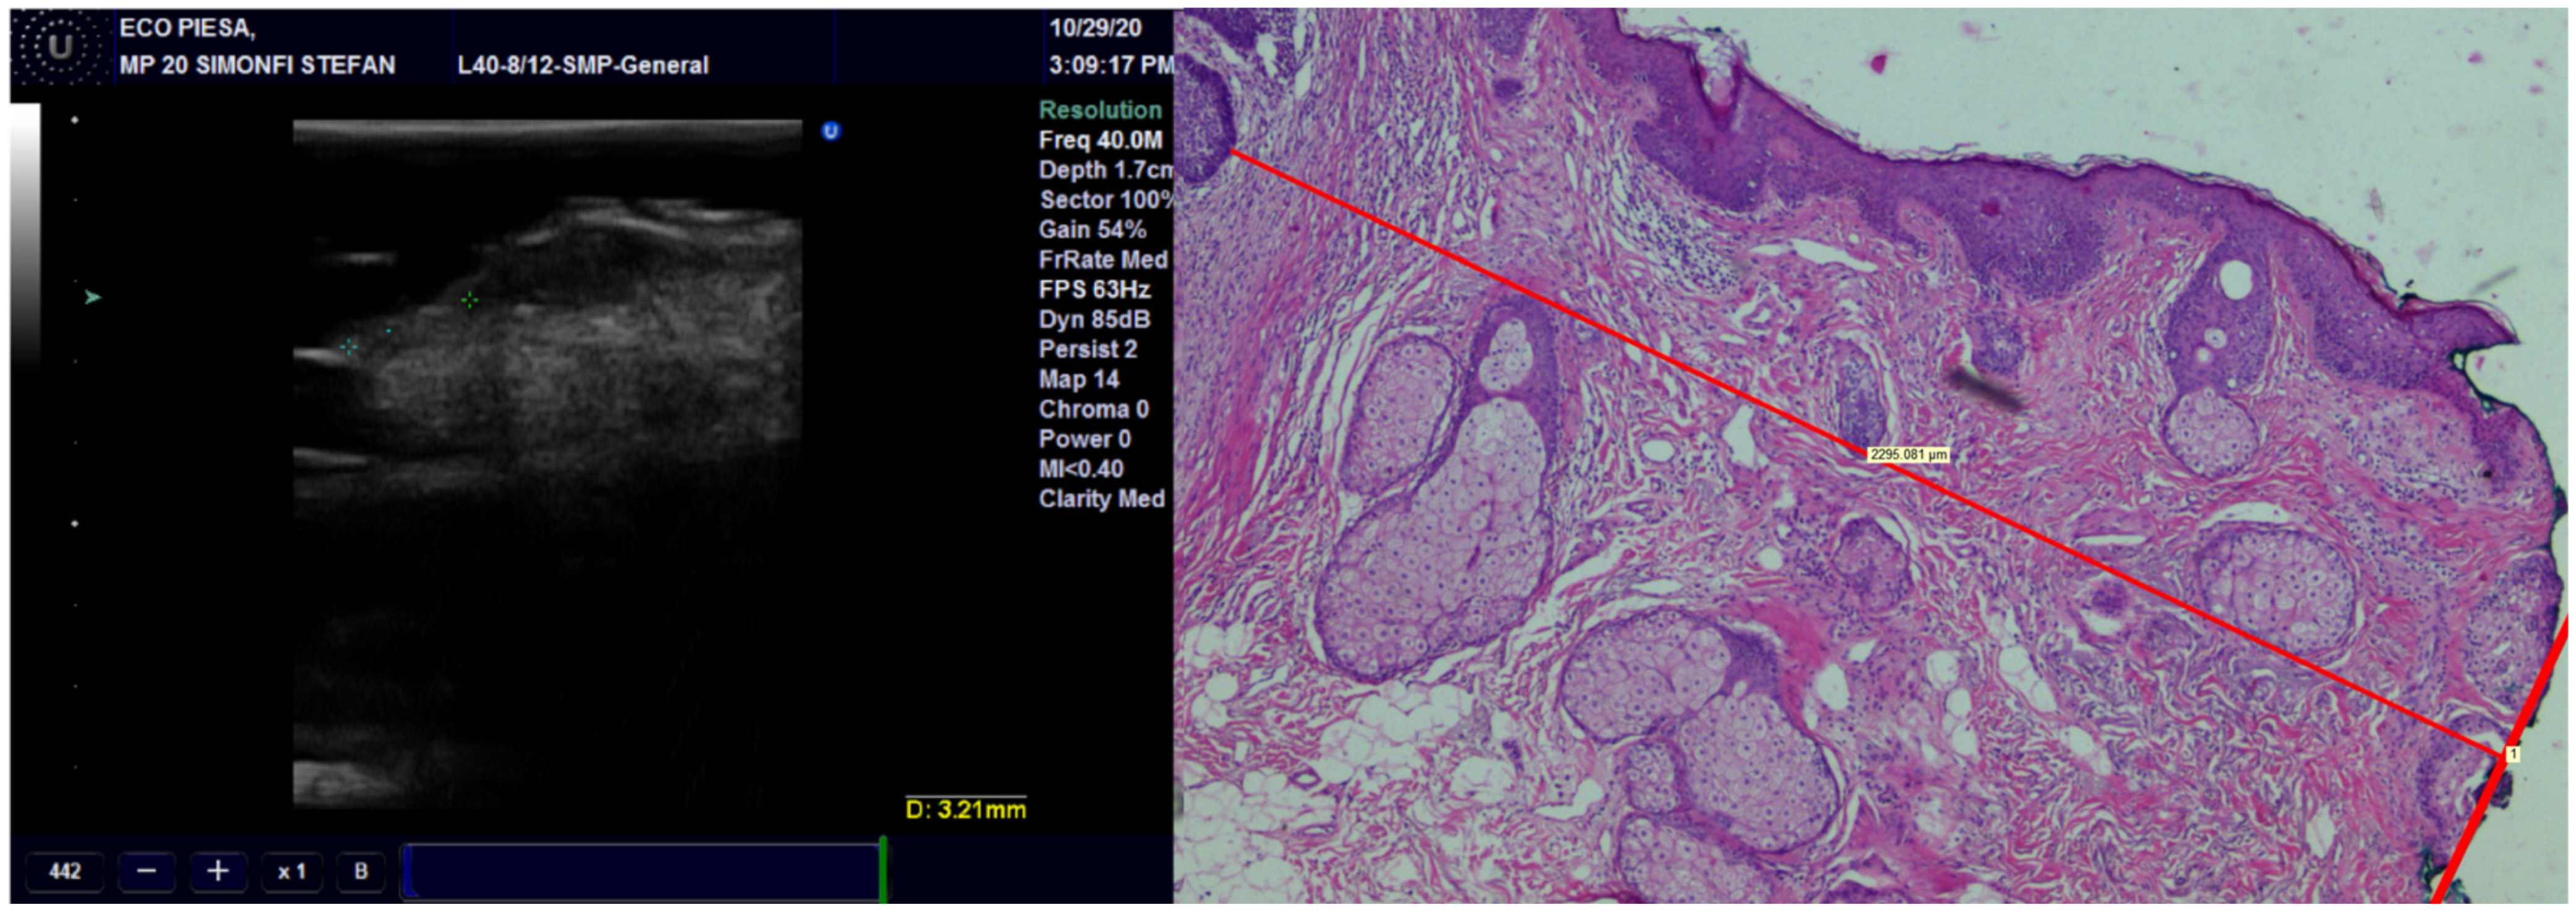

Figure 3.

The thickness of the tumor, measured on US with 20 MHz and 40 MHz transducers, compared with the pathological image of the tumor showing very high occurrence of US.

Concerning concordance between the histopathological and echographic measurements of tumor thickness, we found excellent agreement for all transducers, with the best ones being for the preoperative observations and the least favorable ones being the postoperative observations (Figure 3) (Table 2). Within any of the preoperative and postoperative observations, the 40 MHz transducer fared the best, followed by the 20 MHz transducer and finally by the 13 MHz transducer.